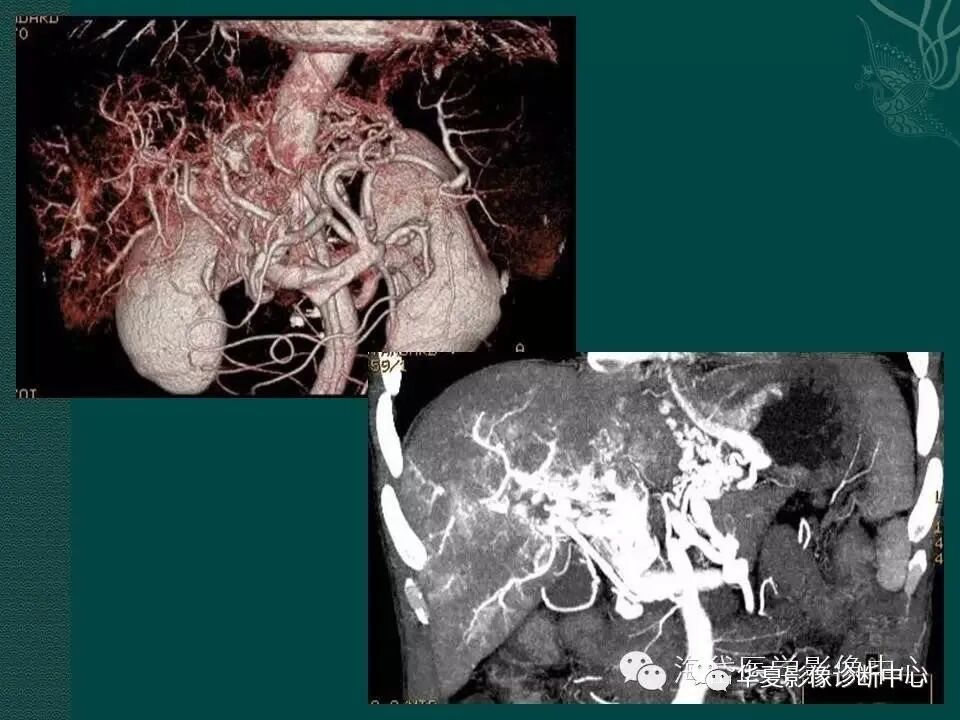

图3 门静脉血栓形成

图4 门静脉主干狭窄闭塞伴侧枝循环建立